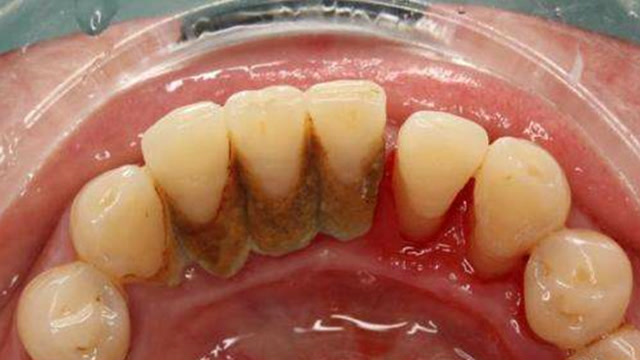

前牙菌斑清除

图片尺寸700x779